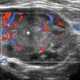

Acute focal pyelonephritis

Pyelonephritis is inflammation of the kidney, typically due to a bacterial infection. Symptoms most often include fever and flank tenderness. [Source: Wikipedia ]